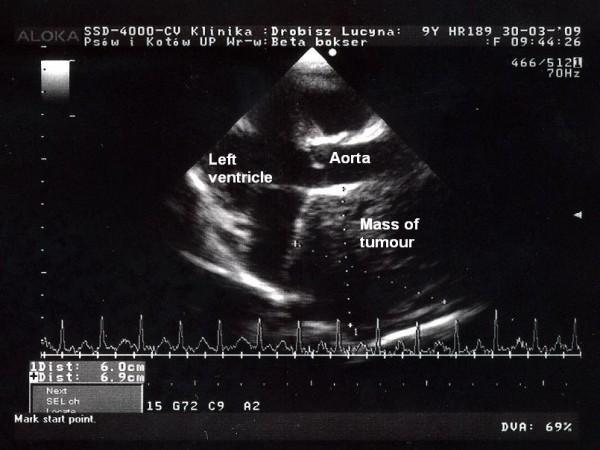

In the period of 3 years, 9 tumours of chemodectoma were supravitally diagnosed and histopathologically verified in dogs. In this period 15 351 dogs were admitted to the Clinic of Dogs and Cats and 2 145 dogs were examined in the cardiological outpatient clinic for dogs. This tumour is located in a typical place--at the base of the heart. Most frequently the tumour manifested in older boxers. Only in one case such a tumour was diagnosed in another breed of dogs. The tumours ranged in size between 3 and 16 cm in diameter. The principal sign accompanying tumours of cardiac base involved dyspnoea but in 3 cases the tumours yielded no clinical signs. All the diagnoses were additionally verified using immunohistochemical examination. We used antibodies to chromogranin A (clone DAK-A3 1:100), synaptophysin (clone SY38 1:20) and neuron-specific enolase (clone BBS/NC/VI-H14 1:150). An immunohistochemical examination is vital for the diagnosis since it allows to differentiate histologically distinct types of neoplasia which may locate in the same site and may manifest a similar histological pattern.

在 3 年的时间里,我们在狗身上成功诊断并通过组织病理学验证了 9 例嗜铬细胞瘤。在此期间,有 15351 只狗到犬猫诊所就诊,有 2145 只狗在犬心脏科门诊进行了检查。这种肿瘤通常位于心脏底部这个典型位置。大多数情况下,这种肿瘤出现在老年拳击犬身上。只有在一个病例中,在另一个品种的狗身上诊断出了这种肿瘤。肿瘤直径在 3 至 16 厘米之间。伴随心脏基底肿瘤的主要症状是呼吸困难,但在 3 例中,肿瘤没有产生任何临床症状。所有诊断均通过免疫组织化学检查进一步验证。我们使用了针对嗜铬粒蛋白 A(克隆 DAK-A3,1:100)、突触素(克隆 SY38,1:20)和神经元特异性烯醇化酶(克隆 BBS/NC/VI-H14,1:150)的抗体。免疫组织化学检查对于诊断至关重要,因为它可以区分可能位于同一部位并表现出相似组织学模式的组织学上不同类型的肿瘤。